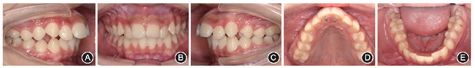

(1)一期矫治:在11、21舌侧窝粘接上颌固定舌刺,纠正不良舌习惯,嘱患者进行舌肌功能训练[3],辅助建立舌体正常功能位置。嘱患者贴口呼吸贴闭唇睡眠,辅以唇肌功能训练[4],纠正口呼吸习惯。矫治1个月的口内像示开

及深覆盖情况有明显改善(图3)。一期矫治用时5个月。

患者矫治1个月时(一期矫治)口内像,示开

及深覆盖改善 A:右侧

像;B:正面

像;C:左侧

像;D:上颌

面像;E:下颌

面像